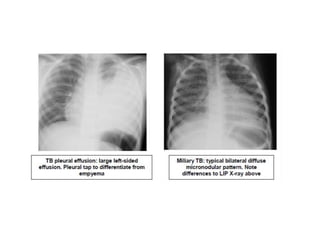

Radiological diagnosis

Chest X-ray

CXR remains an important tool for diagnosis of PTB in children who are sputum smear

negative or who cannot produce sputum

The following abnormalities on CXR are suggestive of Tb :-

• Enlarged hilar lymph nodes and opacification in the lung tissue.

• Miliary mottling in lung tissue

• Pleural or pericardial effusion – though seen on CXR – are forms of extra

pulmonary TB that tend to occur in older children

Radiological diagnosis Chest X-ray CXRremains an important tool for diagnosis of PTB in children who are sputum smear negative or who cannot produce sputum The following abnormalities on CXR are suggestive of Tb :- • Enlarged hilar lymph nodes and opacification in the lung tissue. • Miliary mottling in lung tissue • Cavitation (tends to occur in older children) • Pleural or pericardial effusion – though seen on CXR – are forms of extra pulmonary TB that tend to occur in older children • The finding of marked abnormality on CXR in a child with no signs of respiratory distress (no fast breathing or chest indrawing) is supportive of TB

Primary Tuberculosis onCXR 1.GangliopulmonaryTB ( Characterized by the presence of mediastinal and/ or hilar lymphadenopathy and parenchymal abnormalities, the Ghonfocus 2.TuberculousPleuritis 3.MiliaryTB 4.Tracheobronchial TB